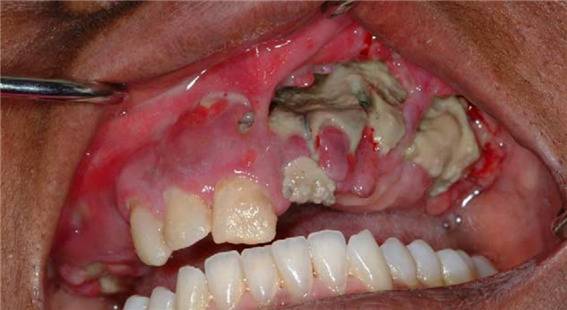

치과 치료 후 발생할 수 있는 무서운 부작용인 '턱뼈 괴사'(ONJ, osteonecrosis of the jaw)가 골다공증약(비스포스포네이트)을 복용한 환자에서 생기는 것이다.

이를 뽑은 후 상처가 아물지 않고 고름이 나오고 턱뼈가 무너져 내려 치료가 매우 힘들고 심지어는 턱뼈를 잘라내는 경우도 있다 하니 끔찍한 일이다.

턱뼈 괴사 보고가 처음 나온 건 2003년이었다. 골다공증약 장기사용 시 생길 수 있는 아주 드문 합병증으로 보고되었다 [6, 7, 8].

하지만 2004년부터 많은 증례가 연이어 발표되면서 턱뼈 괴사에 대해 우려가 점점 고조되었다 [9, 10, 11, 12, 13, 14, 15, 16].

턱뼈 괴사가 발생한 대상이 주로 고용량 주사제를 사용한 암 환자들이었고, 일반인에게서의 발병은 비교적 드물었다. 하지만 치과의사들의 우려를 덜어주기 위해 2005년 말과 2006년 두 차례에 걸쳐 미국치과협회(American dental association)는 특별한 발표를 했다.

하지만 2009년 미국 로스앤젤레스(LA) 남가주(Southern California)대 치대에서 발표한 보고는 가히 충격적이었다. 골다공증 주사제가 아닌 약을 먹은 환자의 4%에서 치과 치료 후 턱뼈 괴사가 생겼고, 심지어 일반적인 통념인 장기 사용자에 국한되는 게 아니라, 단기간(12개월) 사용한 사람에게서도 턱뼈 괴사가 생겼다고 했다 [20].